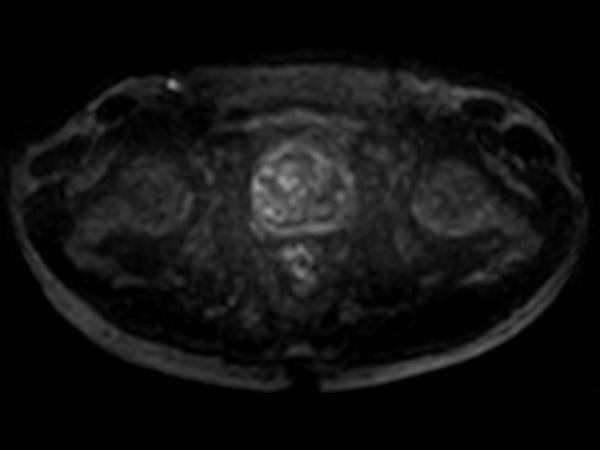

Multi-phase, contrast-enhanced prostate imaging

Patient with a prostate lesion. The ExamCard includes techniques for 3D imaging (PelvisVIEW, eTHRIVE) allowing for multiple image directions in one single scan, efficient fat-free imaging over large field-of-views (mDIXON XD), a multi-phase contrast-enhanced sequence (4D FreeBreathing) to improve imaging confidence and Compressed SENSE to accelerate the entire exam.

DWI b1000

DWI b1000 (ADC)